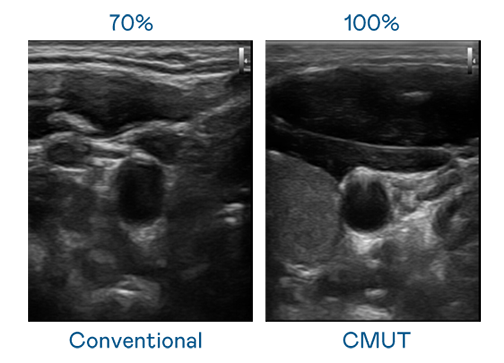

CMUT 技术是一种用电容式微机电元件来产生超音波讯号的技术。与传统 PZT 压电式技术相比,CMUT 频宽增加 30%,更宽频的超音波讯号让影像解析度大幅提升,是实现高影像品质医疗超音波扫描、促进精准医疗发展的关键技术。

超音波影像的解析度高低,首先取决于探头能发出的讯号频宽。j9九游会登录入口首页j988me CMUT 可提供高清晰的超音波讯号,提供高频宽、高灵敏度、影像纹理细节更高的超音波影像,协助医护人员缩短影像判读时间及利用精准的医疗影像进行诊断。